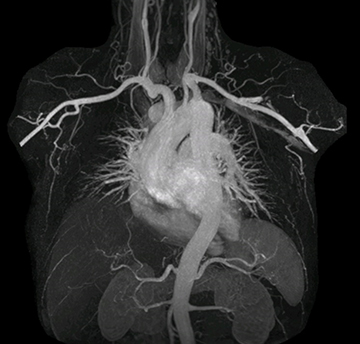

Excellent image quality is obtained in this dynamic scan., C-SENSE factor 5.4, scan time is 1:20 min, voxel size is 0.8 x 0.8 x 1.6 mm, Ingenia Ambition, 1.5T.

Cor 3D T2

“In MRA, the capacity to acquire a sequence in a single breathhold provides images that are motion-free and high in contrast and detail, advantages that aid in diagnosis,” he says. “With Compressed SENSE, we can reduce the time for the single breath-hold to just 2-3 seconds. Before Ingenia Ambition and Compressed SENSE, the breath-hold requirement was about 8 to 9 seconds, which was too long for some patients.”

“In our peripheral MRA run-off studies with Ambition we realize key benefits, including outstanding image quality and significantly reduced breath-hold and scan times, which not only benefit the patient, but also provide the opportunity to add sequences that could aid in diagnosis,” Dr. Peña says.

“Before we had Ingenia Ambition, our CE-MRA run-off studies would first acquire a dynamic pre-contrast scan with 20-25-second breath-holds, then inject the contrast, do another acquisition and then subtract the two,” says Avila. “Now, mDIXON XD allows us to complete the study in just one single pass – without need for a pre-exam – which eliminates subtraction artifacts and almost halves the scan time. In addition, mDIXON provides much better background suppression, which really improves vesselto-background contrast. And, thanks to Compressed SENSE, the single breath-hold is not long and we improve image resolution.”

The subtractionless peripheral MR angiography shows improved vessel-to-background contrast and high resolution. Ingenia Ambition 1.5T.